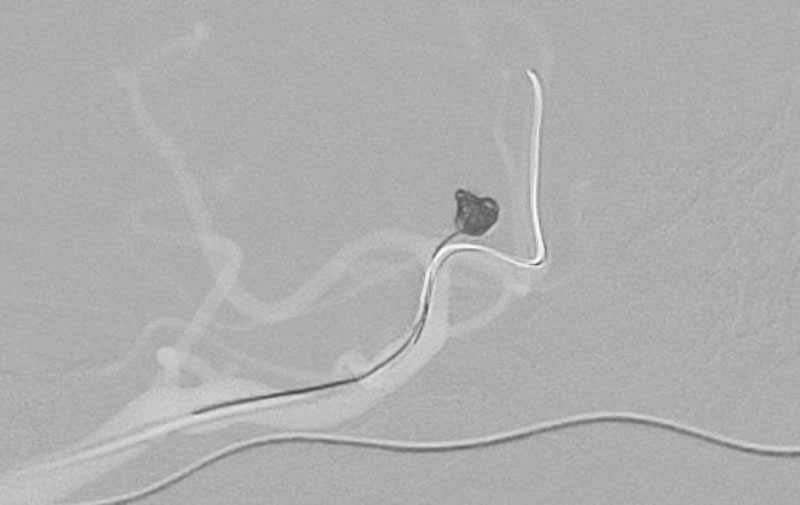

No.1630 手術前

No.1630 手術中

No.1630 手術後